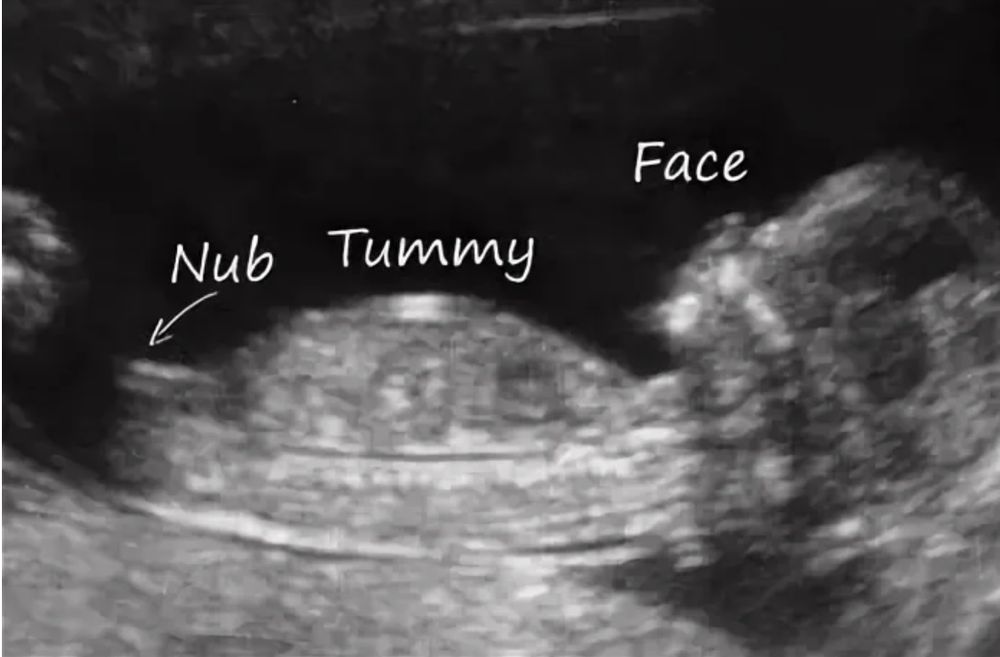

Мальчик или девочка)

Девочка, половой бугорок параллельно спинке. У моих мальчишек он вверх всегда 😁

Буду мамой дочки , вот посмотрите фото, так нагляднее: Изображение Изображение

Похожий снимок предположили девочку 90% надеюсь ниче не отрастет😂

Ракурс сомнительный, но похоже на девочку

Кошка, девочки были правы тут)